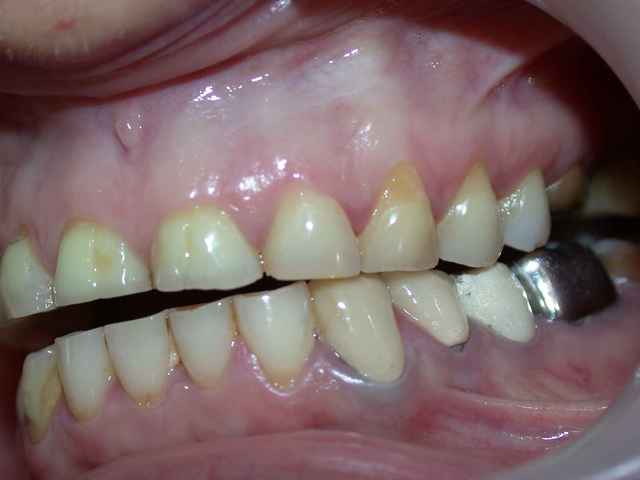

photos et pano du cas initial .

pour poursuivre la fin du cas la pose en mai 2006

du travail conventionnel (que j'espère définitif...)

plusieurs remarques :

je me suis un peu battu avec cette patiente pour la maintenance (bloc incisif inférieur..)

teinte A1 souhaitée par la patiente.

j'ai d'ailleurs réalisé un blanchiment en 2007 des 4 incisives inférieures pour aligner la teinte (en fait une fois que la maintenance a été meilleure ).